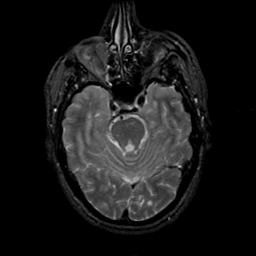

MR Study #21, November 3, 1991 -- Slice #16